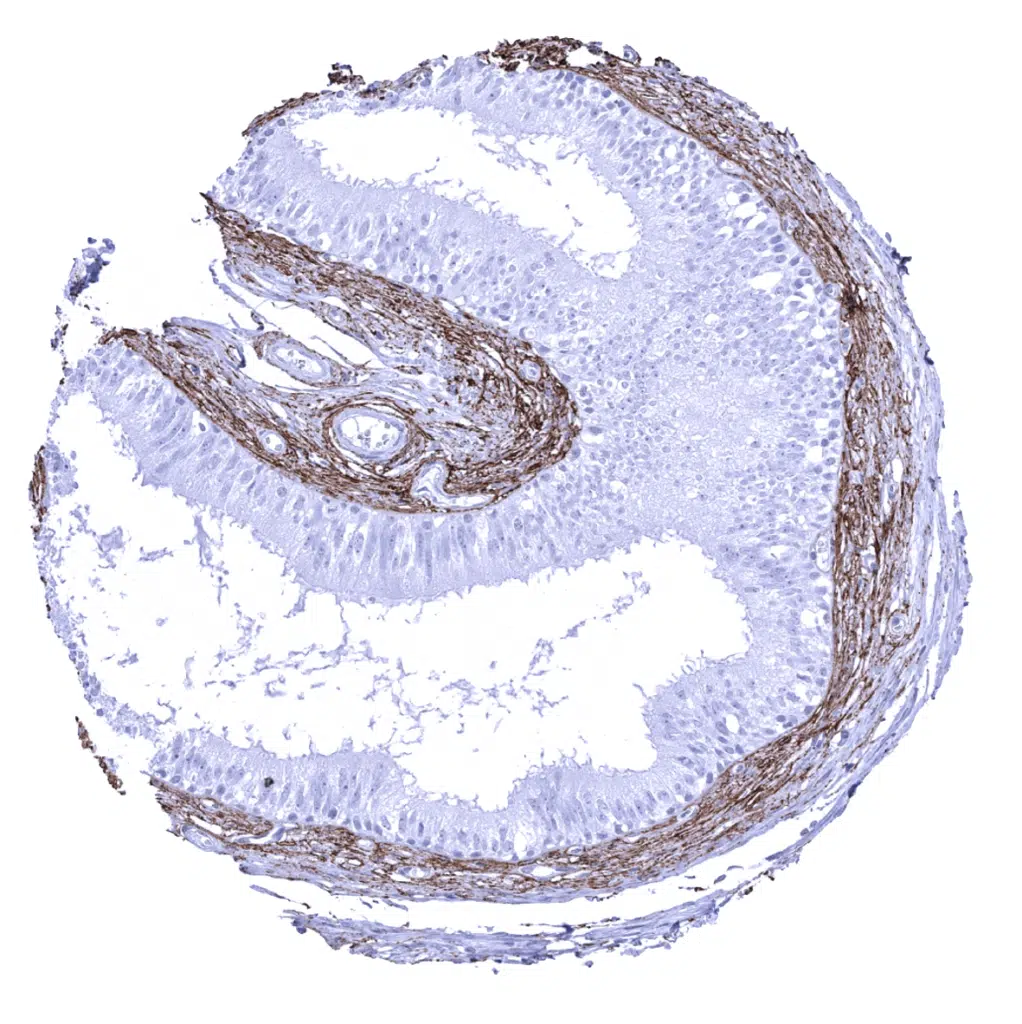

Testis – High density of elastin fibres along smooth muscles surrounding tubuli of the testis.